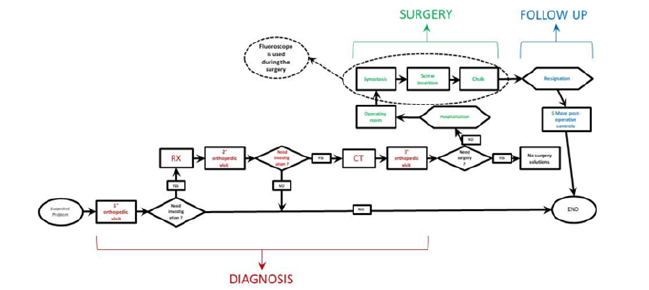

In the first phase of walking, up to 3 years, this condition is completely normal and is part of the physiological growth of the foot. After the age of 3, if the plantar arch isn’t correctly formed, an external action is required such as the use of an arch support. If this does not lead to an improvement of the plantar vault within 8-9 years, corrective surgery is recommended to be performed between 9 and 14 years. The flat foot determines an imbalance of the load at the level of the foot and an imbalance at the level of the posture, therefore can determine the occurrence of painful symptoms. Focusing on subjects of both sexes in infancy-adolescence age (8-16 years) suffering from congenital flat foot from tarsal synostosis, (Figure 3) shows the workflow of the traditional procedure. The main radiological procedure applied are: Radiology (RX) and Computed Tomography (CT). All radiological imaging techniques generally use X-ray beams to represent anatomical structures. The images generated by these methodologies are used to verify the presence of possible pathologies in the anatomical portion subjected to analysis. Of course, X-Ray exposition continues to represent a risk factor for the patient. X- rays produce ionizing radiation, a potentially harmful form of radiant energy. It must be emphasized that the risk of developing cancer following exposure to radiation it is generally contained and depends on at least two factors:

Obtained the tomographic images these are studied in order to carry out a pre-operative planning in which such images are fundamental to define the precise location and orientation of the cut (Figure 3)[4]. Since tomographic images derive from the overlap of 2D images, they can confuse in determining how to proceed with the correct cut of the synostosis. They can also make it difficult to understand how thick the synostosis to be resected is to avoid injury to nearby bones and joints behind the lesion. Considering what was said about exposure to X-rays, the benefit is obvious to find a method that optimizes these first phases both in terms of minimizing the number of radiological examinations and making the tools used in the preoperative planning more efficient. Furthermore, from an economic standpoint, for every RX less the saving is around 22 € while this arise to 87€ in case of CT. (Table 1) shows the overview of the costs and risk of the various procedures that compose this first phase of diagnostic.

Surgical operation

Once the phase of diagnosis is over, we proceed to the surgical operation. During preoperative planning, the most widely used methodology to date is CT, but this is not enough to guide the medical team during surgery. For this reason, the fluoroscope is needed in the operating room. Once again, we use X-rays, this time to try to fill the doubts and uncertainties left by the study of only tomographic images. It would therefore be appropriate for the safety of both the patient and the surgeon, use a technology that monsters from the outset in a manner clear to the anatomy of the malformed foot thus allowing the specialist to intervene with greater safety, also reducing the period of use of the fluoroscope. After resection of the synostosis, the operation continues as in (Figures 4&5) respectively show the step of resection of the synostosis and that of interposition of the material. In some cases, the imperfect outcome of an operation requires a possible surgical revision, the patient will therefore have to undergo an operation very similar to the main one, or to a further CT scan. The costs have also been summarized for this phase (Table 2) which involve the various procedures performed. As can be seen in the, the duration of an intervention of this type is approximately 60 minutes and its cost around €4050.

Post-Operative Stage

For a correct post-operative course, a sequence of 5 orthopedic check-ups are required. These are carried out with a time interval of about 3 months from each other. If after the first 4 visits no problems occurs, during the last visit the removal of the screws will take place, a procedure that requires a small intervention in Day Surgery. The cost of the post-operative stage is listed in (Table 3). (Table 4) summarize the traditional methodology emphasizing the main issues that have been identified during the analysis of the traditional technique.

The Innovative Workflow

For the survey we follow the data obtained by analyzing the pilot study [“3D-printing models in the pre-operative planning of the pediatric patient suffering from congenital malformations”][11]. Thanks to 3D printing, the surgeon can better understand the anatomical condition of the patient. The possibility of developing more detailed surgical plans allows the doctor to achieve better results, safety and speed during the operation. The possibilities to refer to the prototype both before and during the intervention should allow a minor use of the fluoroscope. About the post-operative stage, controls are still performed because they are necessary to ensure that the patient is responding well to the operation. The new workflow is illustrated in (Figure 20).